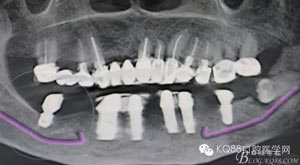

圖2.術(shù)前的CBCT影像檢查:38牙根尖靠近下頜神經(jīng)管。該CBCT是未帶烤瓷冠之前拍的。

隨著種植修復(fù)技術(shù)的普及,很多患者的口內(nèi)會(huì)有種植修復(fù)體,當(dāng)相鄰的種植修復(fù)體旁邊的牙齒,各種原因無(wú)法保留的時(shí)候,需要拔除,對(duì)于我們來(lái)說(shuō)又是一個(gè)新的挑戰(zhàn)。首先我們要保護(hù)種植修復(fù)體不受損壞,其次是要微創(chuàng)拔除無(wú)法保留的牙齒。這樣才能最大限度的保留種植體周圍的骨量。該患者種植術(shù)前沒(méi)有及時(shí)拔除38。導(dǎo)致修復(fù)兩年后38齲壞,引起臨床癥狀,幸運(yùn)的是沒(méi)有種植修復(fù)37,不然,拔除難度會(huì)加大很多。

通過(guò)該病例提示我們大家,下頜第二磨牙缺失,第三磨牙阻生時(shí),如果做種植修復(fù),最好提前拔除阻生第三磨牙。避免以后對(duì)第二磨牙的種植體產(chǎn)生損害。